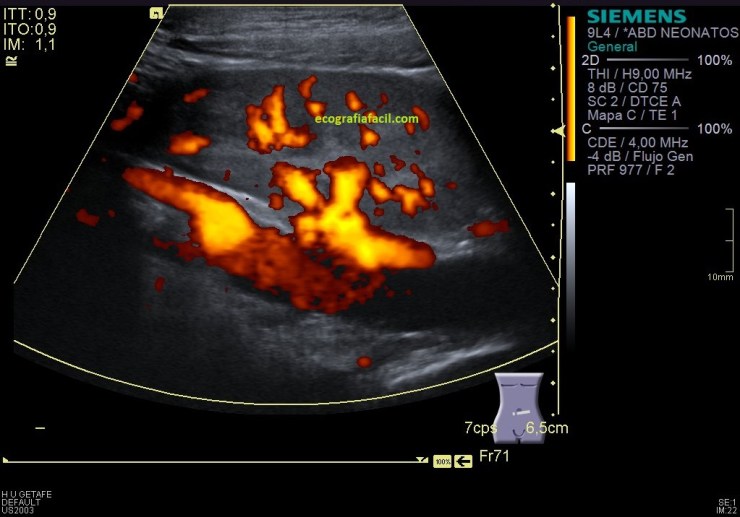

En la imagen 9 y la 10 del RD valoramos la vascularización cualitativa del órgano, vemos que su vascularización es rica, homogénea, de aspecto normal con las dos técnicas. Lógicamente en modo angio o doppler power vemos una vascularización más importante ya que a la vascularización de flujos rápidos (Doppler Color) le sumamos la vascularización de flujos más lentos (Doppler power).